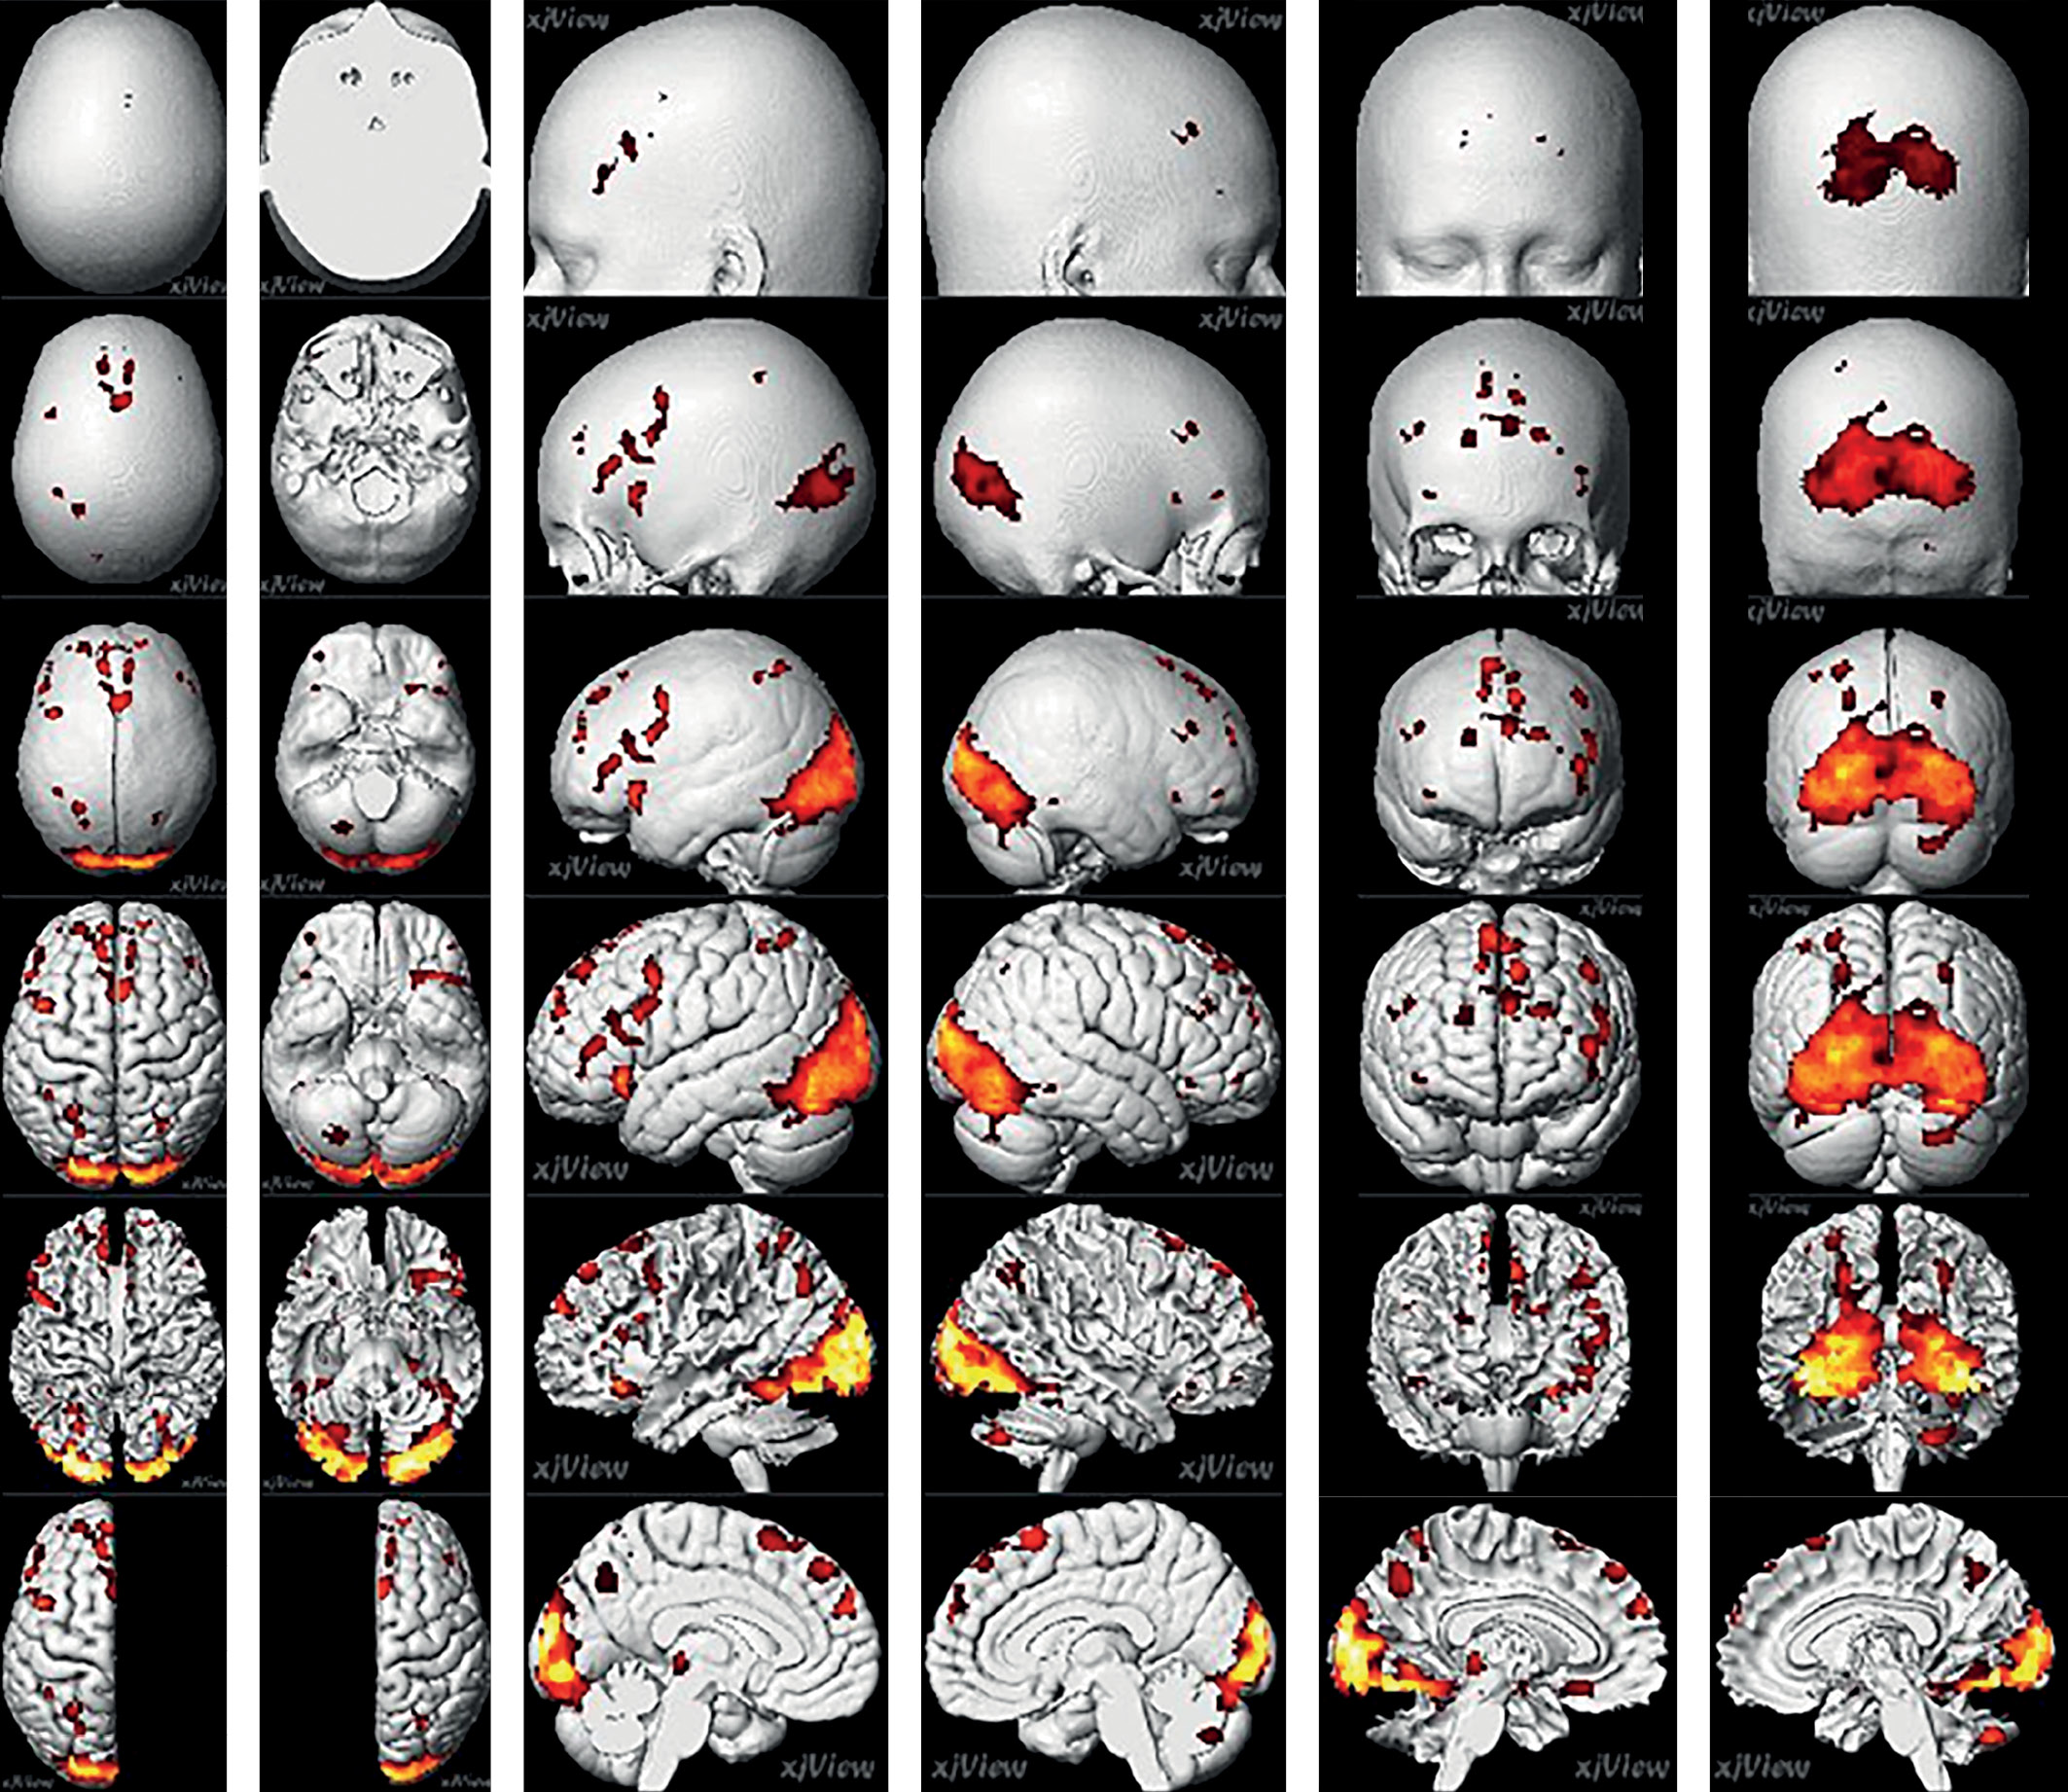

По данным фМРТ с использованием пищевой парадигмы у пациентов c ожирением до лечения обнаружена заинтересованность следующих зон: в обоих полушариях большого мозга — затылочные доли (зрительная кора), верхняя теменная долька (7 ПБ) (вторичное чувствительное поле: представление движения, двумерно-пространственная локализация), ДЛПФК (9 и 46 ПБ, нижняя, средняя лобные извилины); в левом полушарии (ЛП) — нижняя теменная долька (40 ПБ) (интерпретация чувствительных стимулов, письмо, счет, пространственная ориентация), островковая долька (участвует в процессе обработки различных сенсорных импульсов: болевых, обонятельных, вкусовых, а также эмоций, поведенческих реакций), дорсомедиальная префронтальная кора (ДМПФК — верхняя, средняя лобные извилины), задние отделы таламуса (различные виды чувствительности, ноцицепция, интероцепция). Наибольший объем кластера наблюдался в области затылочных долей. Объем зон активации, координаты центров кластеров указаны в табл. 2 и на рис. 1.

После окончания приема сибутрамина повторно выполнялась фМРТ с использованием пищевой парадигмы. Для сравнения выбрали зоны с наибольшей активацией, отмеченной в первом исследовании, — затылочные доли, верхняя теменная долька (7 ПБ), ДЛПФК (9 и 46 ПБ); в левом полушарии — нижняя теменная долька (40 ПБ), ДМПФК, островковая долька, задние отделы таламуса (табл. 3, рис. 2).

Рисунок 1. Зоны активации пациентов до лечения при выполнении парадигмы (групповой анализ).

Figure 1. Zones of activation of patients before treatment when performing the paradigm (group analysis).

Рисунок 2. Зоны активации пациентов после лечения при выполнении парадигмы (групповой анализ).

Figure 2. Zones of activation of patients after treatment when performing the paradigm (group analysis).

Отрицательные значения показателей, приведенные в табл. 4 (в процентном выражении), свидетельствуют об уменьшении объема активации соответствующих зон головного мозга по сравнению с состоянием до лечения, положительные — об увеличении активации. Обращают на себя внимание показатели активации, выявленные в области затылочных долей (зрительная кора) у пациентов с ожирением. Исходно эти показатели были существенно выше, чем в контрольной группе; после лечения отмечалось уменьшение активации ниже установленных референсных значений.

По большинству исследованных кластеров выявлено снижение активации после лечения, за исключением средней и верхней лобных извилин (ЛП) (ДМПФК), а также задних отделов таламуса (ЛП). В первом случае увеличение объема активации составило более 70%.

Сравнение показателей с контрольной группой выявило определенный паттерн различий, в соответствии с которым изначальные уровни активации в большинстве кластеров у пациентов были ниже установленных референсных значений. Тем не менее две зоны продемонстрировали иной характер изменений: в случае средней и верхней лобной извилин (ЛП) исходный объем активации был значительно выше показателей контрольной группы, а после лечения он оказался еще более высоким. В отношении нижней и средней лобных извилин в правом полушарии (ПП) наблюдалась обратная тенденция: исходно высокий уровень активации после лечения снижался и стремился к значениям, характерным для контрольной группы. При сравнении данных по объему активации кластеров в области верхней теменной дольки билатерально обращают на себя внимание уменьшение активации после терапии сибутрамином, а также меньшая степень активации при сравнении с контрольными показателями. В области нижней теменной дольки отмечается также снижение активации как после лечения, так и по сравнению со здоровыми. Островковая доля левого полушария в основной группе до лечения показала меньшую степень активации по сравнению с участниками с нормальным ИМТ и уменьшение степени активации после лечения.